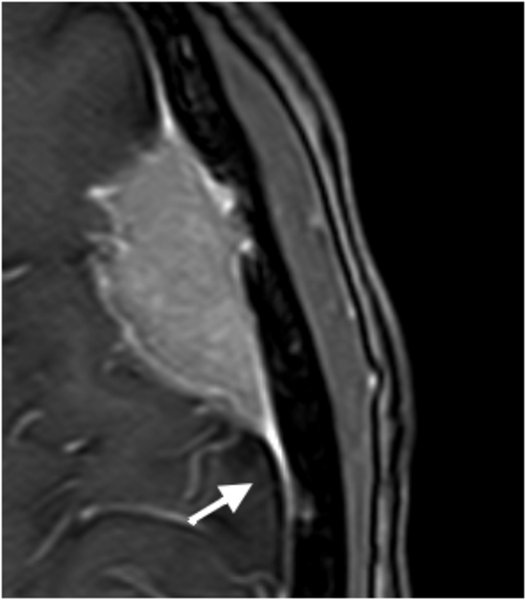

Konvexitätsmeningeom - T1 mit KM

Konvexitätsmeningeom mit charakteristischem "dura tail".